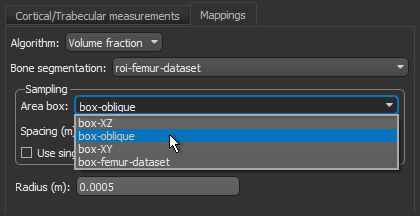

- Choose the settings for each high-definition vector field-based surface anisotropy maps on the Mappings tab, as shown below.

NOTE You can decrease the sampling spacing and radius of influence to 0.0005 m and 0.0015 m, respectively, since you will be computing maps within a sub-volume.